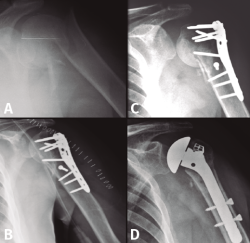

Es probablemente el tratamiento más usado en este tipo de fracturas, normalmente con placas con tornillos de bloqueo poliaxiales en cabeza y tuberosidades, y con tornillos corticales en diáfisis (Figura 3). El uso de suturas irreabsorbibles para mantener la reducción de las tuberosidades también representa un método aceptado para tratar estas fracturas, junto con la placa, las agujas de Kirschner o los clavos de Rush o Ender(9,10), ya que la buena calidad ósea del paciente joven permite un correcta estabilidad de los fragmentos y disminuye la agresividad del procedimiento.

Figura 3. Evolución radiológica de una osteosíntesis con placa de una fractura de húmero proximal derecho. A: radiología simple anteroposterior preoperatoria; B: tomografía computarizada preoperatoria; C y D: evolución radiológica del tratamiento.